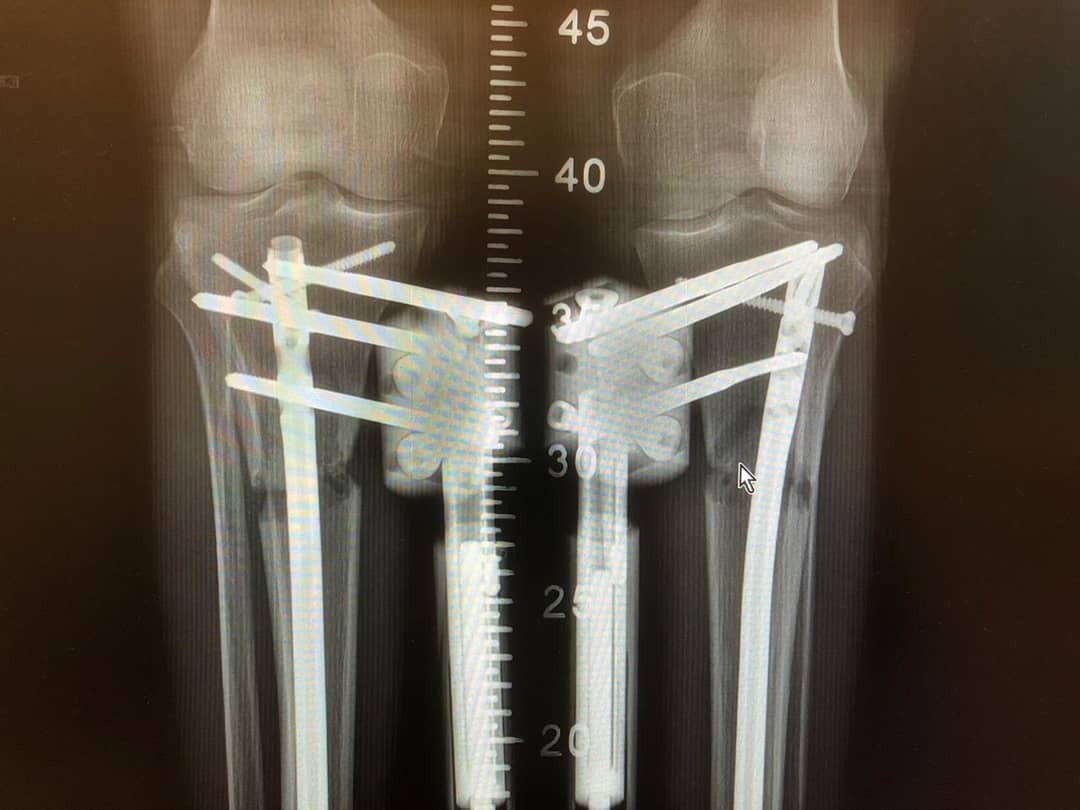

The surgery has two phases: distraction, which involves lengthening the bone and growing new bone; and consolidation which involves making the new bone strong and stable. Problems with growth plates Sometimes there may be a problem with the growth plates in your long bones

'At 40 years old I underwent leg lengthening surgery.' Bone Lengthening Limbs can be lengthened by creating new bone Limb-lengthening can be carried out in the thigh (femur) or lower leg (tibia). Limb lengthening and reconstruction techniques are used to replace missing bone and to lengthen and/or straighten deformed bone segments of legs and arms in children and adults

Limb Lengthening Surgery Procedure, Process & Recovery . This will include experience with management of internal and external fixation, circular frames, lengthening nails and management of bone infection. Typically this takes over 50 days for every centimetre of lengthening